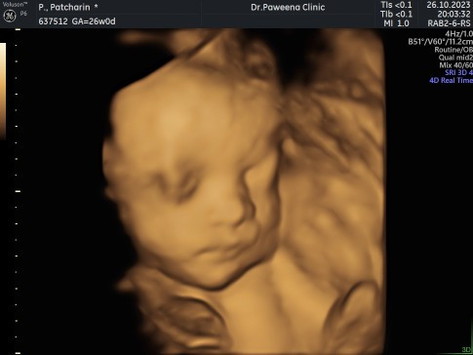

ลูกสาวบ้านนี้ไปขโมยดั่งใครมาค่ะเนี้ย😂 มาอวดรูปกันหน่อย บ้านนี้26+3 ดิ้นเก่งมากก ไม่อยากจะนึกถึงตอนคลอด🥺